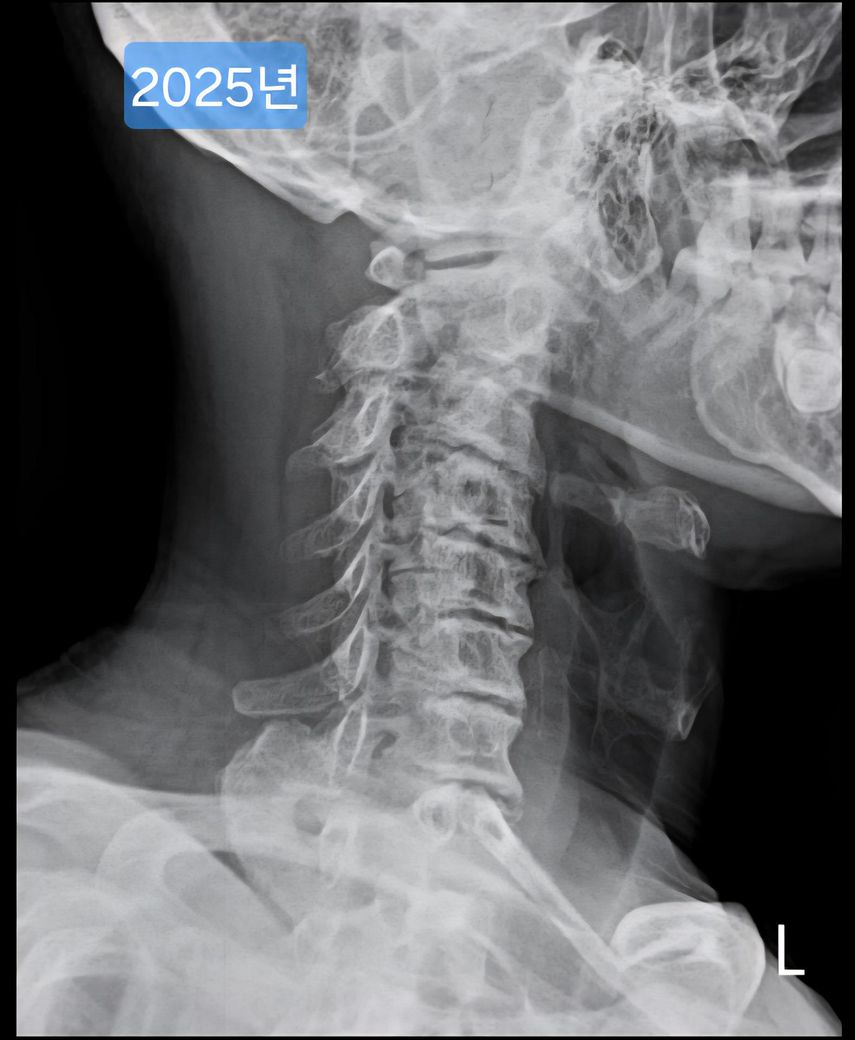

목이 경추사이가 좁고, 일자목인데 헬스를 해도 될까요?

선생님이 같이 찍힌 목사진을 보시더니 심각하다며..경추사이 간격도 좁고, 일자목이고..

며칠전 찍은 2025년도 엑스레이와 9년전 사진을 업로드 해 드리겠습니다.

(이미지에 좌측상단에 해당연도 표시했습니다.)

• 1번 째 사진

• 2번 째 사진